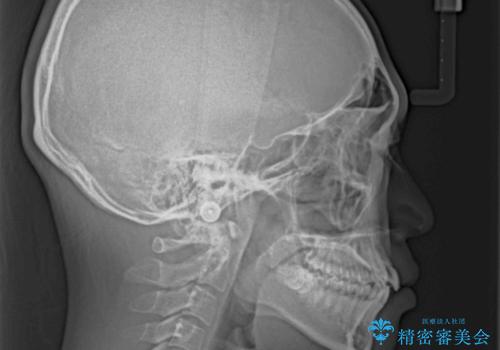

- 八重歯と口元の閉じにくさを気にして来院された患者様です。

非抜歯矯正で歯列を整えると、治療後に口元が今よりも突出する可能性が高かったため、上下左右の第一小臼歯4本を抜歯し、ワイヤー装置にて矯正治療を行うこととしました。